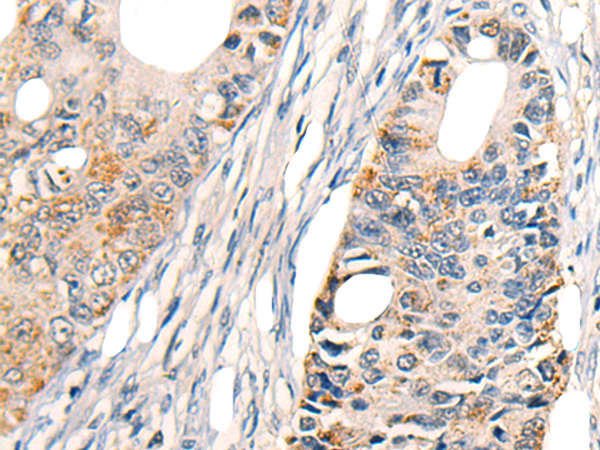

分类: 科研抗体货号: P06202别名: AMY; CLAC; CLACP; CFEOM5; CLAC-P应用: WB,IHC反应种属: Human, Mouse